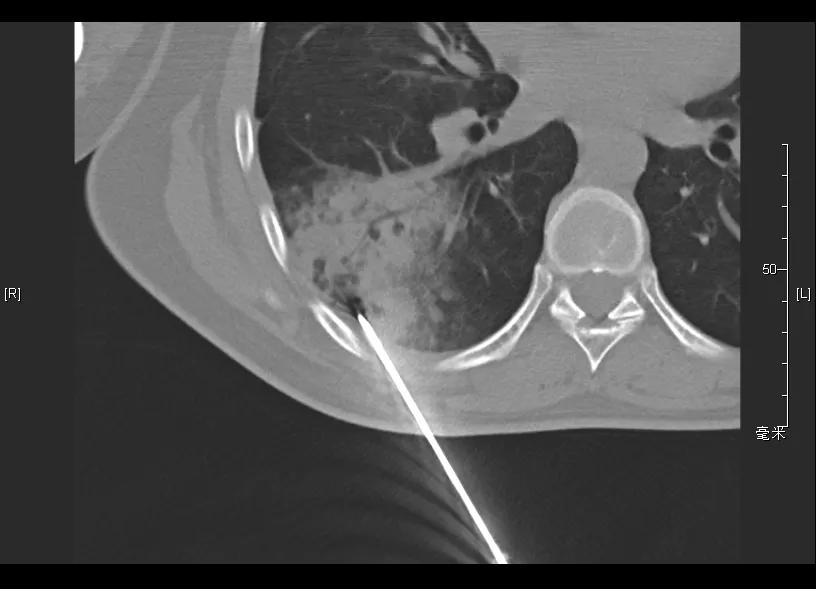

胸部CT(2019-08-19):右下肺新发炎症病变;余两肺炎性病变,较前相仿。

补充辅助检查: T-SPOT:A/B(76/46),隐球菌荚膜抗原 阴性,G试验、GM试验 阴性;自身抗体阴性。

CT引导下肺穿刺活检(2019-08-20)

病理报告: (经皮CT引导右下肺斑片造穿刺活检)少量肺组织,肺泡间隔增宽,部分区域可见类上皮细胞巢和淋巴细胞浸润。免疫组化示肉芽性病变,伴肺泡上皮增生和T淋巴细胞浸润,特殊染色见抗酸阳性杆菌。免疫组化:CD68{KP1}(示组织细胞丰富),CK{pan}(上皮+),Ki-67(25%阳性),LCA(淋巴细胞+),CK7(上皮+),CD3(较多淋巴细胞+),CD20(少数淋巴细胞+)。特殊染色:PAS(-),抗酸(+),六胺银(-),网染(网状纤维+)。

再次调整治疗方案

开始予四联抗结核:异烟肼0.3g qd po,利福平0.45g qd po,乙胺丁醇0.75g qd po,吡嗪酰胺0.5g tid po

停用硫唑嘌呤;糖皮质激素逐步减量至停用。